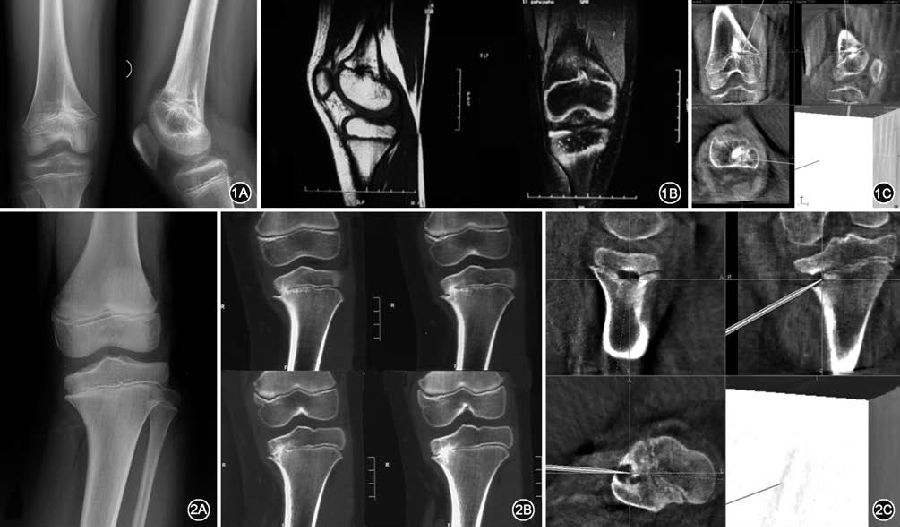

图1 10 岁男性股骨远端骺早闭,术前影像与术中导航相匹配 1A.术前X 线片显示股骨远端偏内侧骺早闭,形成中央型骨桥;1B.术前磁共振示在矢状位和冠状位上骺线中断,骨桥形成;1C.术中导航影像清晰显示出冠状位、矢状位、水平位的骨桥位置,图中所指为磨钻到达位置,引导下进行磨除 图2 11岁男性胫骨近端骺早闭,术前影像及术中骨桥磨除后再次导航确认 2A.受伤3 年后逐渐出现胫骨近端内翻畸形,术前平片未发现明确骨桥;2B.术前CT 检查发现胫骨近端部分层面可见边缘型骨桥;2C.术中磨除骨桥后再次导航,骨桥部位已变成空腔,术中应用指示器于空腔内各点确认骨桥完全磨除